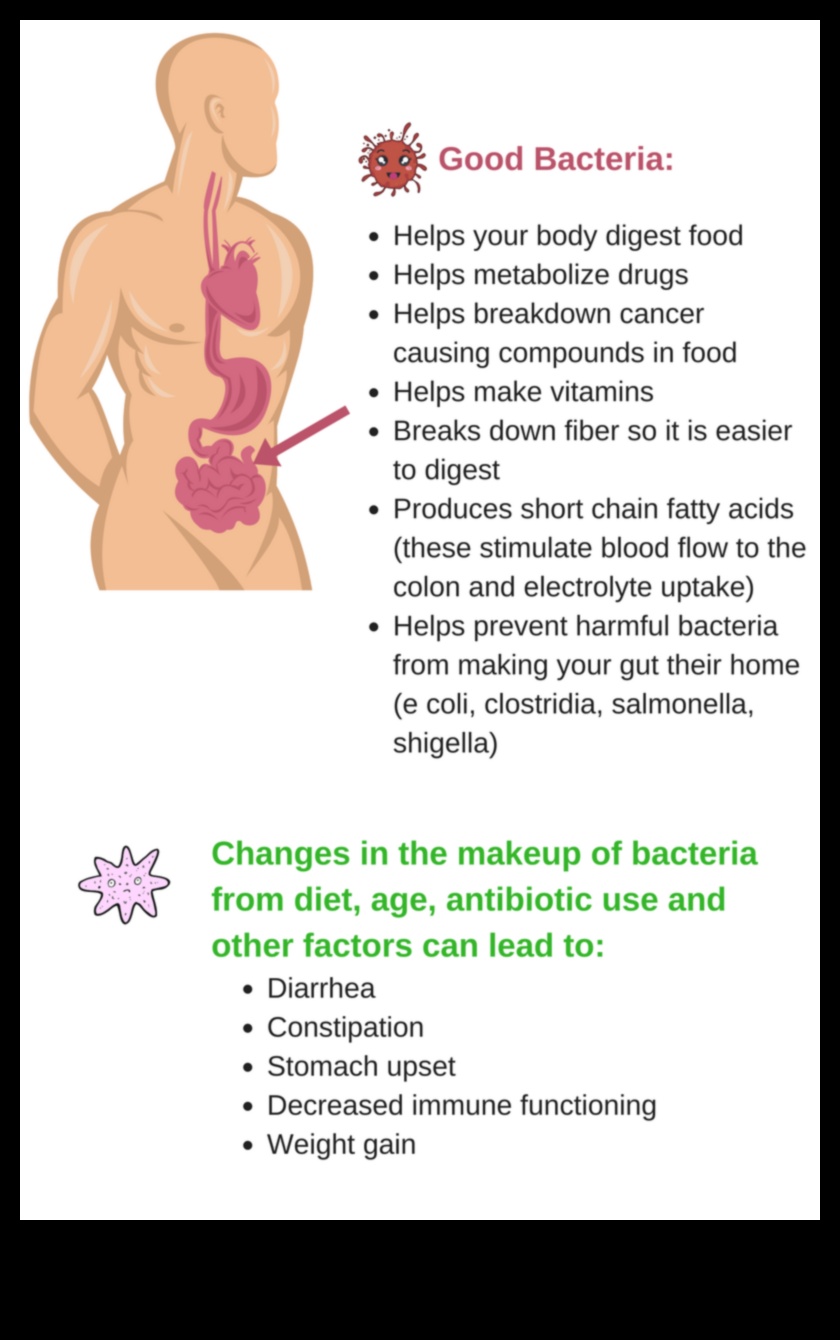

Чревната микробиота е група от трилиони микроорганизъм, вируси и други микроорганизми, които пребивават в човешкия храносмилателен тракт. Тези микроби играят жизненоважна задача в храносмилането, имунитета и метаболизма и все до каквато и да е степен по-нататък се свързват със липса на тегло и наднормено тегло.

В допълнение, някои изследвания показват, че някои пробиотици и пребиотици могат ще можем ли помогнат за насърчаване в съответствие с липса на тегло. Пробиотиците са живи микроорганизъм, които биха могли да бъдат намерени във ферментирали ястия еквивалентен на кисело мляко и кефир. Пребиотиците са несмилаеми въглехидрати, които хранят полезните микроорганизъм в сърцето. И пробиотиците, и пребиотиците могат ще можем ли помогнат за подобряване храносмилането, мащабиране в съответствие с възпалението и насърчаване в съответствие с липса на тегло.

Здравият чревен микробиом е прикрепен с многобройни предимства за липса на тегло, заедно с:

- Повишена ситост

- Намалено дразнене

- Подобрена инсулинова чувствителност

- Повишен разход в съответствие с мощност

Тези ползи могат ще можем ли помогнат за по-лесното намаляване на теглото и поддържането му.

В допълнение, здравият чревен микробиом може допълнително ще можем ли помогне за защита от наднормено тегло и други хронични болести.